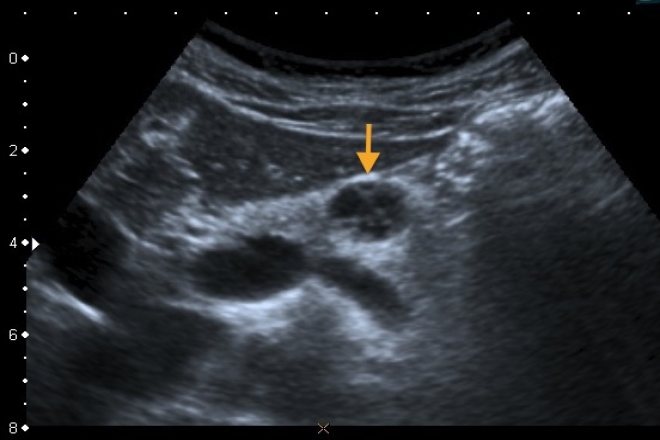

La localización del tumor es difícil sobre todo en los gastrinomas o insulinomas ya que suelen medir dos centímetros de diámetro. El aspecto más característico de los tumores neuroendocrinos  es el de una tumoración redondeada, hipoecogénica, homogénea con límites precisos y refuerzo periférico, mientras que los insulinomas son intrapancreaticos en el 99% de los casos los gastrinomas en el 40 a 70% de los casos.

La ultrasonografía endoscópica aporta imágenes de alta resolución  del parénquima pancreático por lo que puede distinguir lesiones de hasta 2-3 mm de diámetro. Los tumores neuroendócrinos generalmente son tumores pequeños y solo los no secretantes o no funcionantes suelen ser voluminosos. Las lesiones son hipo o isoecogénicas, bien delimitadas, pareciéndose a las adenopatías. La USGE se puede considerar como el método diagnóstico inicial de elección para evaluación y manejo de pacientes con sospecha de TNE, también aporta información fundamental sobre la extensión locorregional. A pesar de esto no se debe olvidar que las pruebas de imagen convencionales siguen siendo decisivas para detección de metástasis a distancia.

La USE se considera una técnica segura, muy sensible y coste efectiva para localización preoperatoria de estos tumores, además con la punción con   aguja fina  PAAF guiada por USE aumenta la sensibilidad y puede ser especialmente útil en tumores no funcionantes.